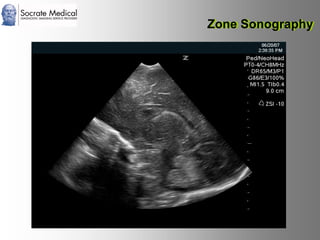

Il documento presenta la tecnologia della zone sonography, che promette una rivoluzione nel campo degli ultrasuoni, superando i limiti dei sistemi tradizionali grazie a metodi di acquisizione dati più veloci e una gestione delle informazioni migliorata. Questa tecnologia consente una maggiore definizione dell'immagine, una riduzione degli artefatti e un'ottimizzazione del processo diagnostico, con vantaggi in termini di tempo e costi. Inoltre, il channel domain processing e la zone speed technology offrono applicazioni avanzate e miglioramenti nella sicurezza diagnostica.